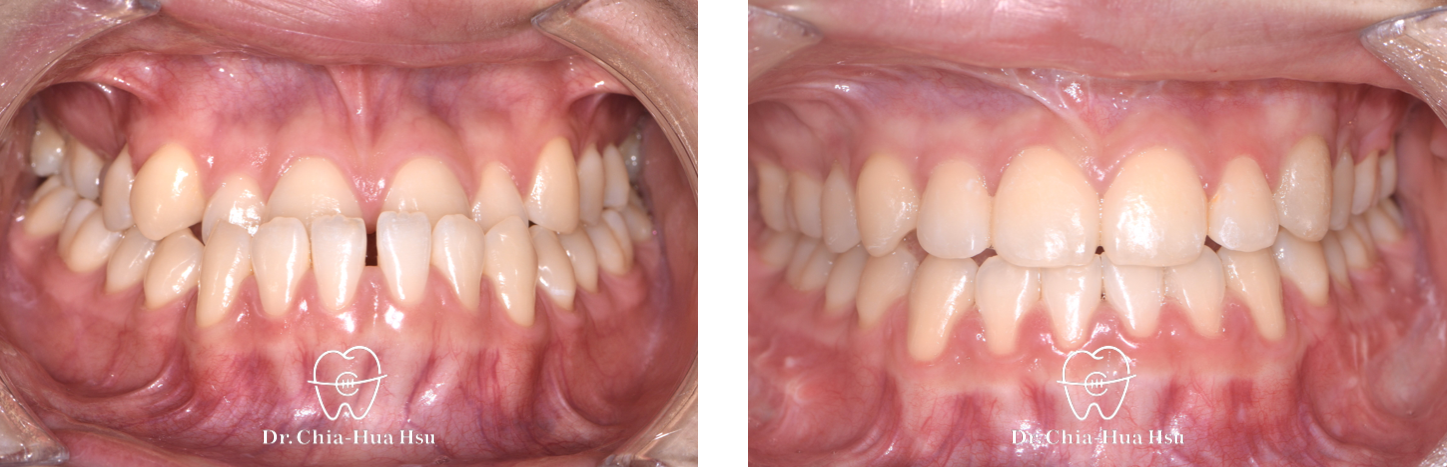

治療前

治療後

• 問題分析:患者是標準的骨骼三類咬合(Skeletal Class III),下巴明顯較長,還有上顎牙弓過窄、開咬以及齒列不正。

• 治療方式:使用傳統金屬矯正器,合併正顎手術(雙顎),上顎拔除兩顆小臼齒以利手術方式進行上顎牙弓擴寬。

• 治療結果:齒列排齊,咬合功能恢復,外觀更和諧。